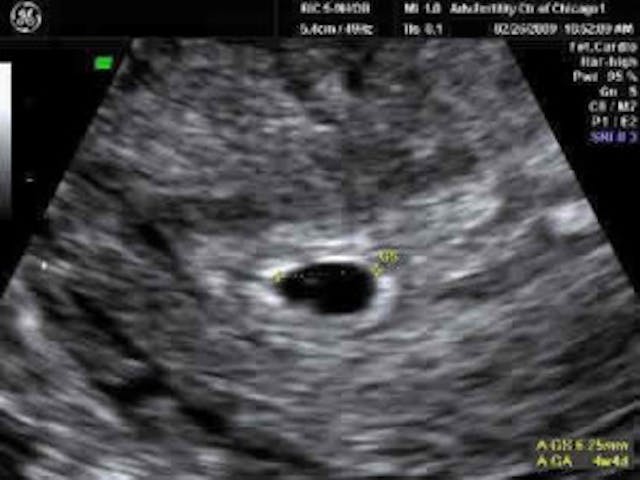

The first, and most damning, piece of evidence to come to light is that Emily Letts is a failed actress. It also turns out that the Abortion Care Network held an “abortion stigma busting competition”, which had a cash prize for the winners. And yes, her video won. Letts also claimed to be only two to three weeks pregnant — highly suspicious no matter which way you look at it. She never said whether it was two to three weeks after her last menstrual period, which would be far too early to measure a pregnancy via ultrasound. And an ultrasound is how doctors determine gestational age. So was it two to three weeks after conception, or two to three weeks after her last menstrual period? If it was two to three weeks after conception, that would actually make her about five weeks pregnant. But seeing anything at five weeks pregnant via an ultrasound is extremely difficult — yet Letts claims that she has an ultrasound photo of the baby she killed, a photo she says she will treasure forever. This is what an ultrasound would look like at the stage of pregnancy she claimed to be at: